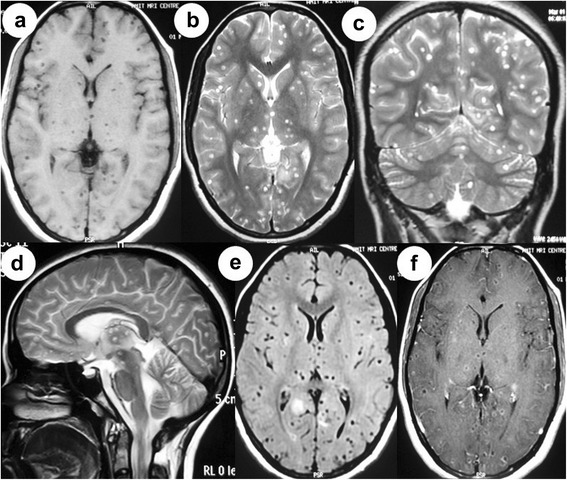

Hemogram, serum biochemistry and x-ray chest were normal. Human immunodeficiency virus (HIV) was negative. Enzyme linked immunosorbent assay (ELISA) was strongly positive for Taenia solium. Ocular B-scan ultrasonography (USG) revealed septations and debris in vitreous in both eyes. It also showed cystic lesion with small peripheral solid nodular area in subretinal space in both eyes [Figure 1(a)]. Orbital computed tomography also depicted the vitreous hemorrhage with retinal detachment in both the eyes. Magnetic resonance imaging (MRI) of orbits showed heterogeneous hyperintensity in posterior chamber of eyes [Figure 1(c), (d)]. Ocular B-scan USG, orbital computed tomography and MRI orbit were consistent with vitreous hemorrhage and retinal detachment in both the eyes (right more than left). Subretinal cyst was located at the posterior pole of both the eyes. MRI brain revealed multiple small cystic intraparenchymal lesions in bilateral cerebral and cerebellar hemispheres, basal ganglia, thalami and brainstem. MRI T1-weighted image showed isointense to hypointense lesions. Fluid attenuated inversion recovery (FLAIR) and T2-weighted images showed hyperintense lesions with surrounding edema. Postcontrast T1-weighted image showed multiple ring enhancing lesions [Figure 2(a-f)].

Figure 2.

MRI brain showing multiple small cystic lesions in bilateral cerebral hemispheres, brainstem and bilateral cerebellar hemispheres with ring enhancement (a-f).